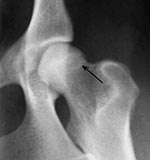

Morgan LinieWeitere Kriterien zur Beurteilung sind die Kongruenz von Oberschenkelkopf und Gelenkpfanne, die Weite des Gelenkspaltes, die Pfannenkontur, die Kontur des Oberschenkelkopfes sowie das Vorhandensein von Hinweisen auf arthrotische Prozesse wie walzenförmige Verdickungen des Oberschenkelhalses, Randwülste an der Gelenkpfanne, unter dem Knorpel befindliche Verdichtungen der Knochensubstanz im Pfannenbereich und die Einlagerung von Knochenmaterial am Ansatz der Gelenkkapsel (Morgan-Linie).